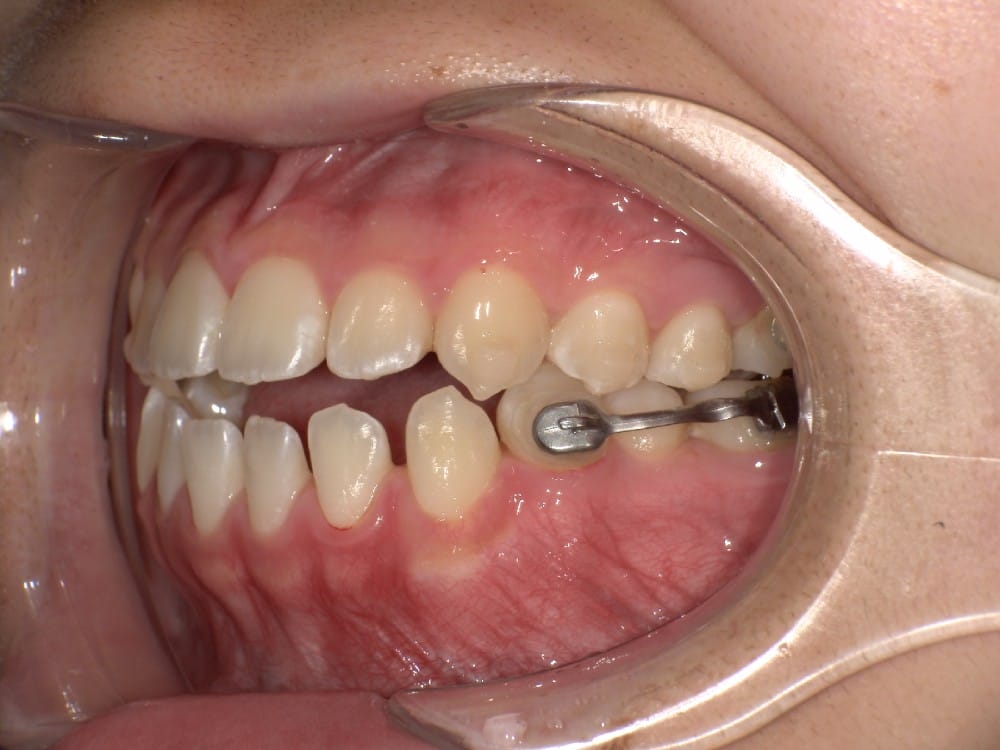

このような奥歯の移動量が大きい症例では、マウスピースだけでは難しいことがあり、カリエールとよばれる装置を補助的に使用し、上下の噛み合わせの前後関係を整えることで、手術を行わずに機能面と見た目の両方が改善することがあります。

一時的に前歯は噛み合わせが開いていますが、受け口の矯正では、最終段階で前歯ばっかりあたって奥歯がしっかり噛まないということも起こりやすいので、あえて狙って動かしています。

ここから上下透明なマウスピースに変え、仕上げていきました。

今回のケースも奥歯の移動量が大きいため、マウスピースだけでは難しいと判断し、カリエールとよばれる装置を補助的に使用し、上下の噛み合わせの前後関係を整えることで、手術を行わずに機能面と見た目の両方が改善することにしました。